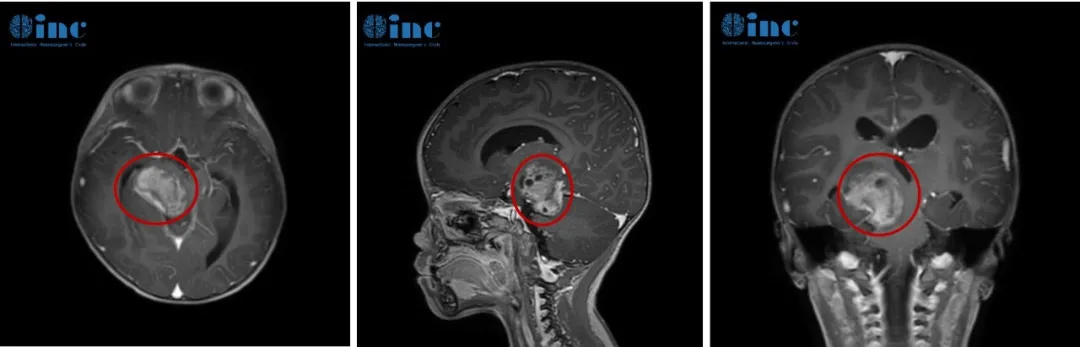

一名12岁少年遭遇两次脑干出血,生命垂危,多位神经外科专家均指出,手术治疗伴随极高风险,术后可能出现失明、失语、瘫痪等严重并发症。然而,若放弃手术,下一次出血事件可能带来毁...